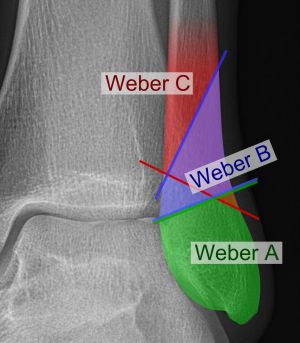

Classification (Danis-Weber System)

- System based on level of the fibular fracture and characterizes stability of fracture

- Tibial plafond and the two malleoli is referred to as the ankle "mortise" (or talar mortise)

Type A

- Fibula fracture below ankle joint/distal to plafond

- Medial malleolus often fractured

- Tibiofibular syndesmosis intact

- Usually stable: occasionally requires ORIF

Type B

- Fibula fracture at the level of the ankle joint/at the plafond

- Can extend superiorly and laterally up fibula

- Tibiofibular syndesmosis intact or only partially torn

- No widening of the distal tibiofibular articulation

- Medial malleolus may be fracture

- Possible instability

- Use gravity or weight bearing stress X-rays to determine stability [1]

Type C

- Fibula fracture above the level of the ankle joint/proximal to plafond

- Tibiofibular syndesmosis disrupted with widening of the distal tibiofibular articulation

- Medial malleolus fracture

- Unstable: requires ORIF